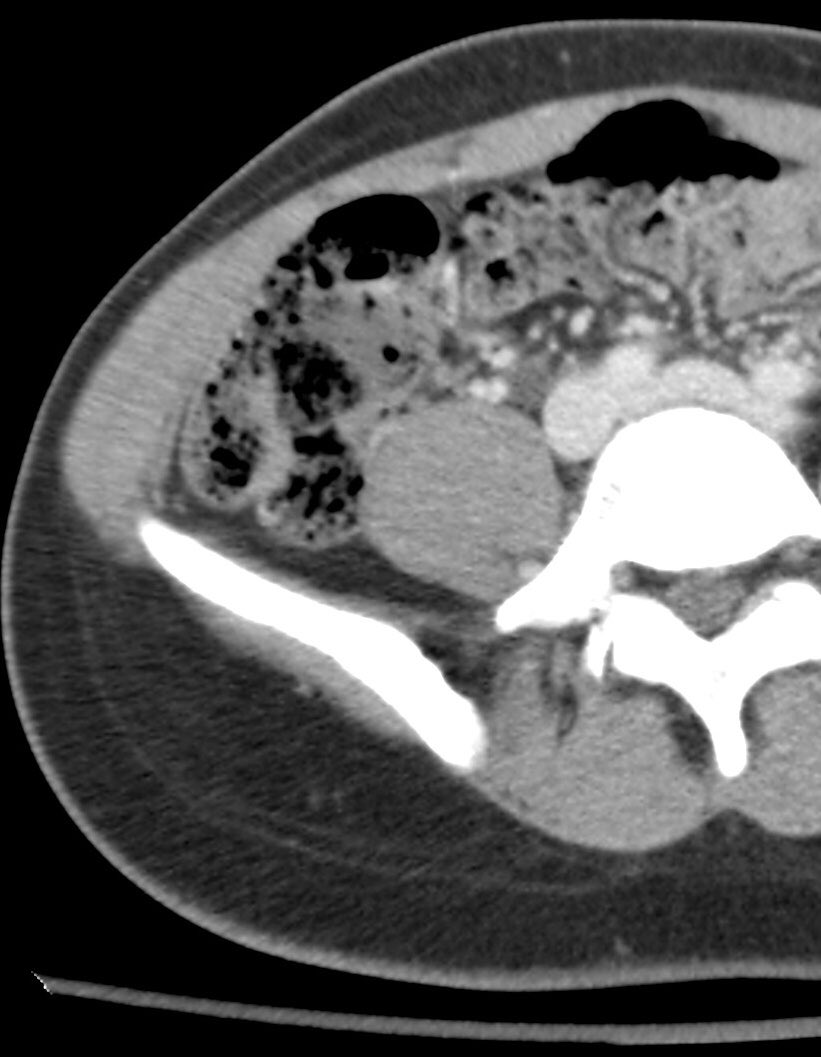

What’s going on with the cecum in this 30yo woman with AML, hematochezia and melena and neutropenia? Last image from prior study for comparison

#meded @cooperradresidency@CooperGME@CooperHospital @cbmandepi#medtwitter#radres pic.twitter.com/URf8O0kBtc